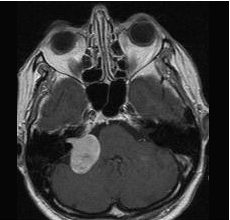

- T1W image + iv. contrast material (enhancement is seen in the right ponto-cerebellar angle: Schwannoma.)